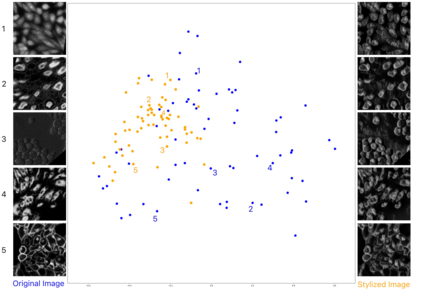

Deep-learning models have been successful in biomedical image segmentation. To generalize for real-world deployment, test-time augmentation (TTA) methods are often used to transform the test image into different versions that are hopefully closer to the training domain. Unfortunately, due to the vast diversity of instance scale and image styles, many augmented test images produce undesirable results, thus lowering the overall performance. This work proposes a new TTA framework, S$^3$-TTA, which selects the suitable image scale and style for each test image based on a transformation consistency metric. In addition, S$^3$-TTA constructs an end-to-end augmentation-segmentation joint-training pipeline to ensure a task-oriented augmentation. On public benchmarks for cell and lung segmentation, S$^3$-TTA demonstrates improvements over the prior art by 3.4% and 1.3%, respectively, by simply augmenting the input data in testing phase.